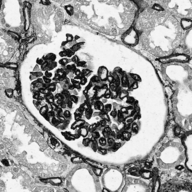

Image datasets in digital pathology applications often consist of consecutive slides stained differently, each staining providing specific information on the same region of interest (see Figure 1, first row). Even though differently stained slides appear very different, there is often a significant amount of consistent information between them. For example, they may both share the same counterstain (e.g. haematoxylin), or they may highlight different parts of the same structure.

Objects to be segmented, e.g. glomeruli, are generally easily identified between stainings as globally they exhibit the same structure and texture, see Figure 1. It should therefore be possible to bias the network to learn stain invariant features. This work investigates this possibility by modifying the data presented to the network in an unsupervised manner. Borrowing domain adaptation terminology, herein the staining used for training and validation is referred to as as the source staining (irrespective of any transformations), and the stainings to which the network are applied as target stainings.

Next is a strategy to extract biological information that is consistent across different stainings—the haematoxylin counterstain. Despite this biological plausibility, it does not result in good results. Indeed, the haematoxylin transformed images vary greatly between the different stainings (see Figure 1, second row). Several factors may explain this: 1) haematoxylin’s concentration relative to the primary stain may vary from one staining to another, resulting in different shades of blue and fixation amount; 2) as a counterstain, haematoxylin may become mixed with another stain in structures that are targeted by both. These result in a color mixing that is in practice not perfectly unmixed by a color deconvolution algorithm.